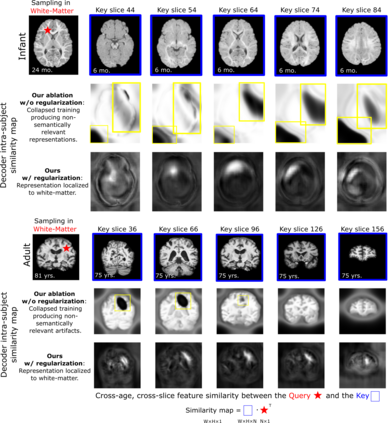

Recent self-supervised advances in medical computer vision exploit global and local anatomical self-similarity for pretraining prior to downstream tasks such as segmentation. However, current methods assume i.i.d. image acquisition, which is invalid in clinical study designs where follow-up longitudinal scans track subject-specific temporal changes. Further, existing self-supervised methods for medically-relevant image-to-image architectures exploit only spatial or temporal self-similarity and only do so via a loss applied at a single image-scale, with naive multi-scale spatiotemporal extensions collapsing to degenerate solutions. To these ends, this paper makes two contributions: (1) It presents a local and multi-scale spatiotemporal representation learning method for image-to-image architectures trained on longitudinal images. It exploits the spatiotemporal self-similarity of learned multi-scale intra-subject features for pretraining and develops several feature-wise regularizations that avoid collapsed identity representations; (2) During finetuning, it proposes a surprisingly simple self-supervised segmentation consistency regularization to exploit intra-subject correlation. Benchmarked in the one-shot segmentation setting, the proposed framework outperforms both well-tuned randomly-initialized baselines and current self-supervised techniques designed for both i.i.d. and longitudinal datasets. These improvements are demonstrated across both longitudinal neurodegenerative adult MRI and developing infant brain MRI and yield both higher performance and longitudinal consistency.